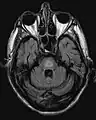

El antecedente de haber sufrido hiponatremia, sumado a las características clínicas previamente descritas son el sello de la enfermedad. La resonancia magnética puede mostrar ciertos cambios a nivel del parénquima cerebral, como es el aumento en la intensidad a nivel pontina[4]

Galería de imágenes

Mielinolisis central pontina

Resonancia que muestra aumento de la intensidad de la imagen bilateral y simétrica a nivel del caudado (flecha pequeña), putamen (flecha larga) con extensión hasta el globo pálido, sugerente de mielonisisi extrapontina